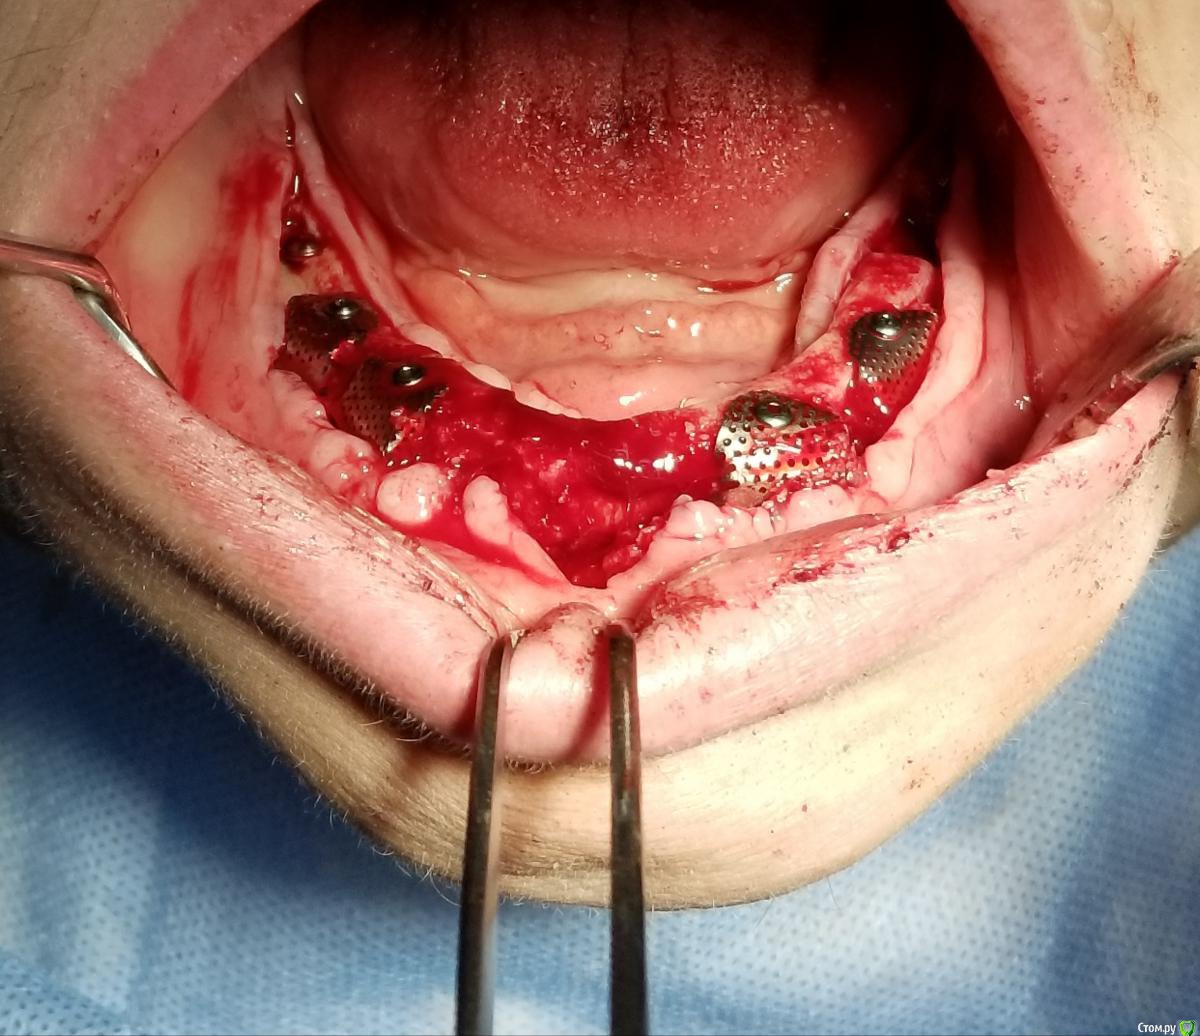

Kostoprav Опубликовано 14 июня, 2019 Поделиться Опубликовано 14 июня, 2019 Ксено+ауто +i prf, поверх титановых мембран перикард. кт через 5 мес.при и создании прикрепленки использовалась свиная дерма отечественного производителя 4 Ссылка на комментарий

vgraev Опубликовано 20 июня, 2019 Поделиться Опубликовано 20 июня, 2019 спасибо за клинический случай! скажите,пожалуйста, это сетки,фиксированные заглушками, или смарт билдеры со спейсерами? Ссылка на комментарий

Kostoprav Опубликовано 28 июня, 2019 Автор Поделиться Опубликовано 28 июня, 2019 спасибо за клинический случай! скажите,пожалуйста, это сетки,фиксированные заглушками, или смарт билдеры со спейсерами?сетки фиксировал спейсерами Ссылка на комментарий